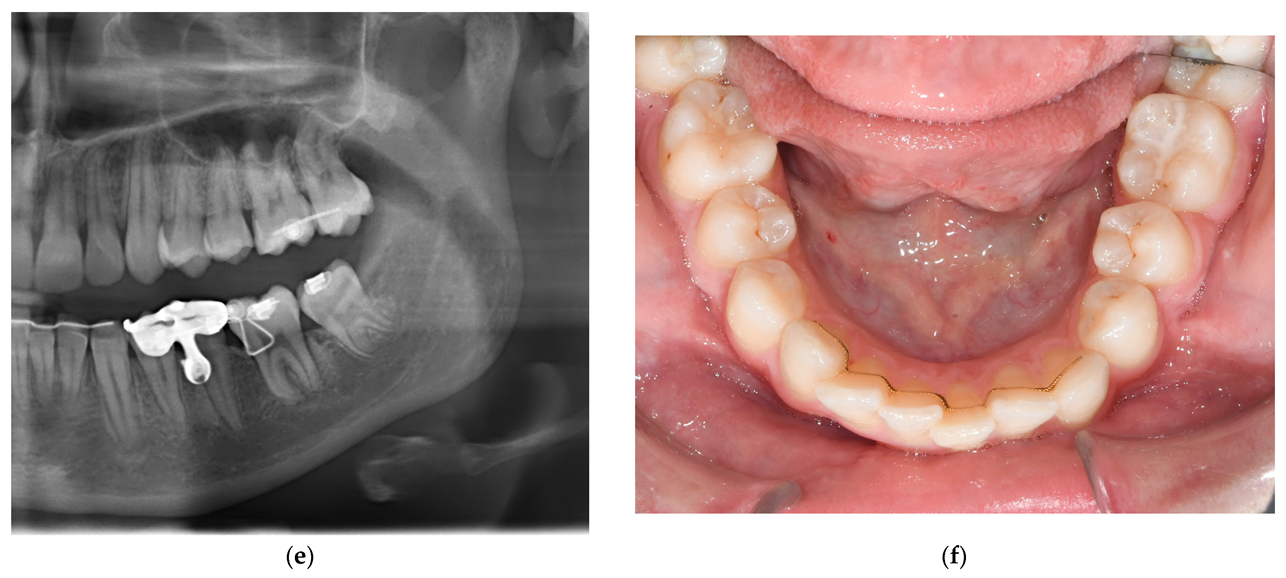

3.3. Treatment Progress

3.4. Treatment Results